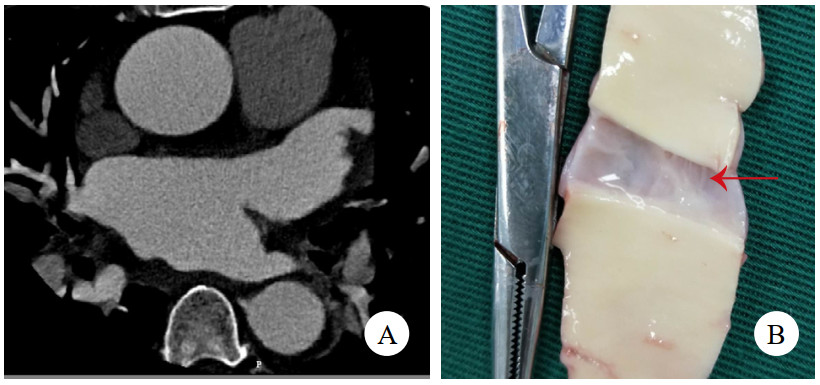

病例3,男,60岁,因“半小时前晕厥1次”就诊。送入抢救室时见患者大汗淋漓,显著呼吸困难,查体:心率97次/min,血压76/52 mmHg(1 mmHg=0.133 kPa),精神极软,颈静脉怒张,心音低钝,未及心脏杂音。立即查床边TTE,见大量心包积液(图 3A)。符合心包填塞,予心包穿刺,见血性液体流出约100 mL后,患者胸闷缓解,心率下降,血压138/88 mmHg。查主动脉CTA,见升弓交界靠上腔静脉侧LIT(图 3B,C,D),该处主动脉直径为31 mm,局部外膜薄层血肿形成。建议手术,患方拒绝,在抢救室留置6 h后生命体征突然消失,后宣布临床死亡。

| 注:A为TTE,箭头示大量心包积液伴血块;B为CTA横断面,箭头示内膜片;C为CTA冠状面,箭头示内膜片;D为CTA多平面重建,箭头示内膜片 图 3 例3患者TTE及CT影像 |

病例4,男,63岁,因“活动后胸闷、气促6年,加重1月”入院。TTE提示二尖瓣前叶A2区腱索断裂伴脱垂、重度返流,主动脉瓣重度返流,三尖瓣中度返流,左心室显著增大,左心室舒张末期直径86 mm,心功能减低,中重度肺动脉高压,升主动脉内径增宽直径43 mm。冠状动脉CTA提示双侧冠状动脉无显著病变,少量心包积液,未见主动脉根部病变(图 4A)。术前准备后,择期手术,术中见主动脉前壁窦管交界水平一长约2 cm的内膜撕裂符合LIT。仔细观察切除标本(图 4B),见内膜裂口边缘光滑,考虑为陈旧性改变。予行Bentall加二尖瓣机械瓣置换加三尖瓣成型术。术后康复顺利,规律抗凝随访1年。

| 注:A为冠状动脉CTA,未见异常;B为切除的主动脉壁,箭头示内膜裂口 图 4 例4患者CT影像及主动脉壁照片 |